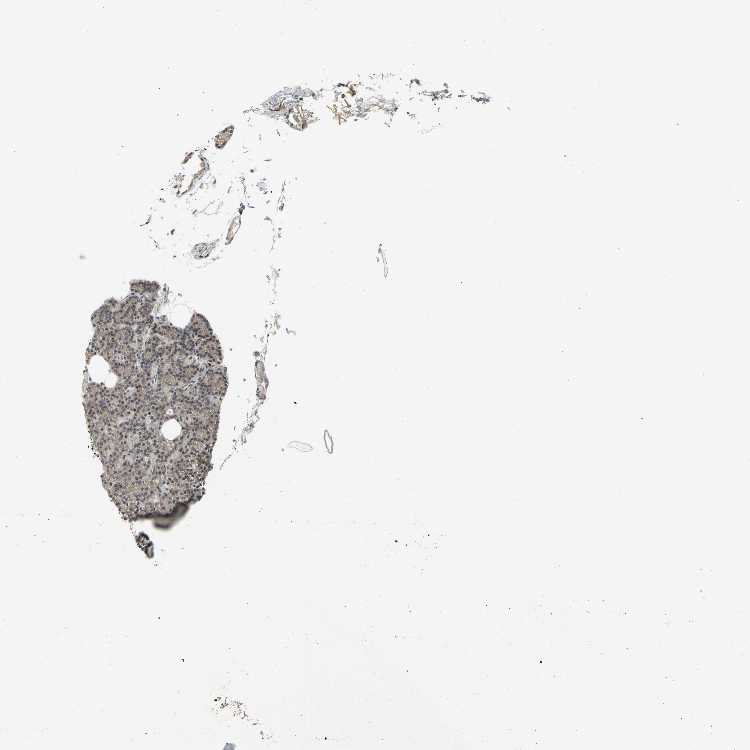

TISSUE PRIMARY DATA PARATHYROID GLAND Show tissue menu

PARATHYROID GLAND - Antibody stainingi

Antibody staining in the annotated cell types in the current human tissue is reported as not detected, low, medium, or high, based on conventional immunohistochemistry profiling in selected tissues. This score is based on the combination of the staining intensity and fraction of stained cells.

Each image is clickable and will lead to virtual microscopy that enables deeper exploration of all samples and also displays staining intensity scores, fraction scores and subcellular localization as well as patient and tissue information for each sample.

Antibody HPA006914Antibody CAB004563

Glandular cells MediumLow